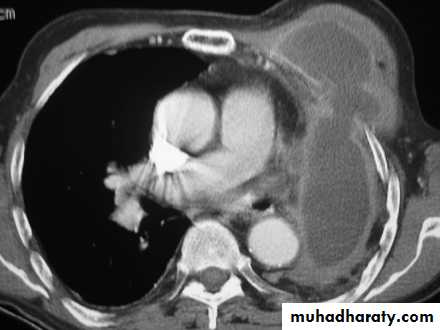

• CT image shows empyema and draining chest wall abscess.

• Empyema necessitans : is a rare complication of empyma occurs when the infected fluid discharge spontaneously into the chest wall from the pleural space result from inadequate treatment of an empyemaInvestigations

• CXR shows a loculated pleural effusion. The enhanced axial CT scan for another patient shows a characteristic enhancement of both the visceral and parietal pleura, a sign of pleural inflammation that occurs with an empyema.